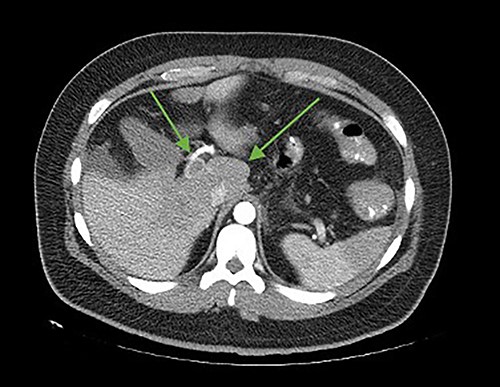

On the seventh postoperative day, he began with abdominal pain, tachycardia, fatigue, and anorexia, limited fluid intake and minimal ambulation. On the eighth day, the patient presented to the emergency department due to intolerance to oral feeding, acute abdominal pain (VAS 8/10), in antalgic position, tachycardic and diaphoretic. Physical examination revealed abdominal hyperalgesia and hyperalgesia. Laboratory tests revealed hemoglobin of 11 g/dl, 18 700 leukocytes (95.3% neutrophils), C-reactive protein of 13.3 mg/dl. Blood gases with pH 7.42, lactate 1.6 mmol/L. A contrast-enhanced abdominopelvic tomography showed portal, mesenteric, and splenic vein thrombosis associated with jejunal wall thickening with adjacent mesenteric changes and free fluid in the cavity (Figs 1 and 2).

Axial cut. In the arrows, lack of opacification of the portal vein with its hyperdense walls, inferior vena cava, lack of splenic opacity.